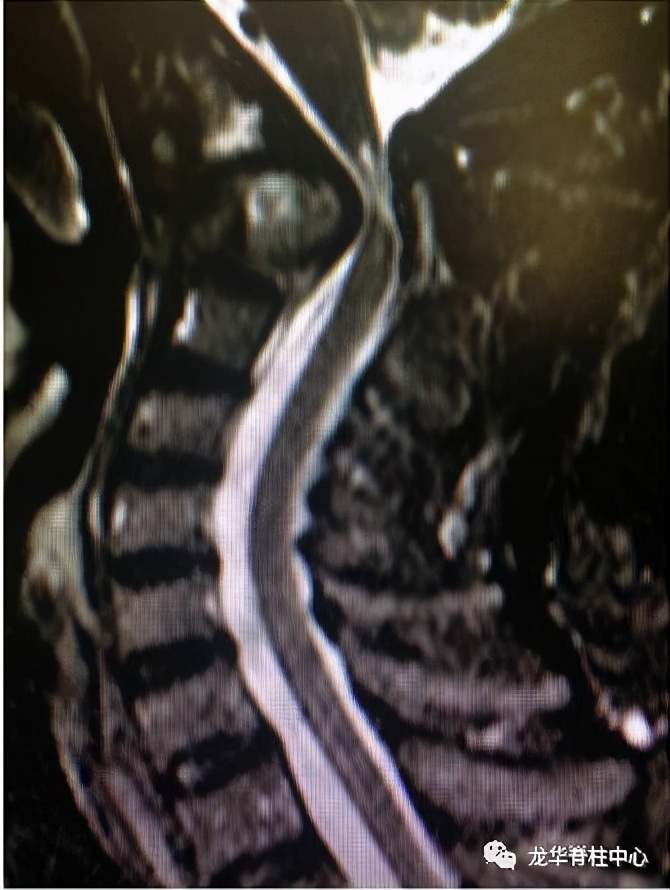

显微镜下寰枢椎脱位经口松解、后路固定术

开展深圳市首例寰枢椎脱位经口咽松解、后路椎弓根钉板内固定术